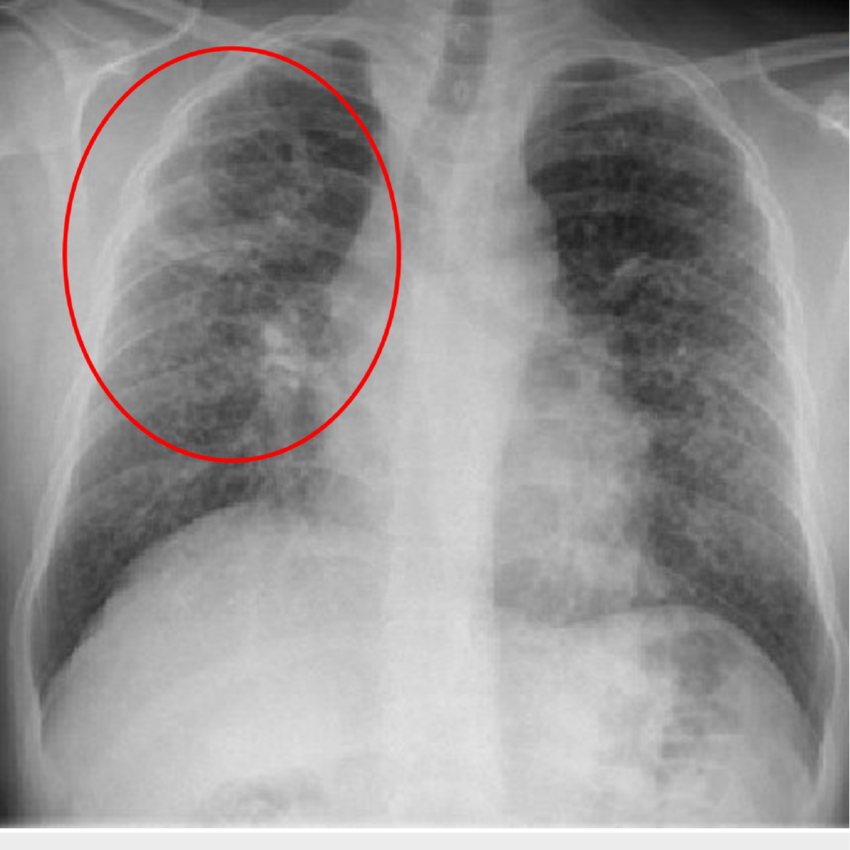

What are the 2 different types of pneumonia on a chest X-ray?

Lobar pneumonia:

Bronchopneumonia:

What type of pneumonia is shown in this image?

this image shows lobar pneumonia